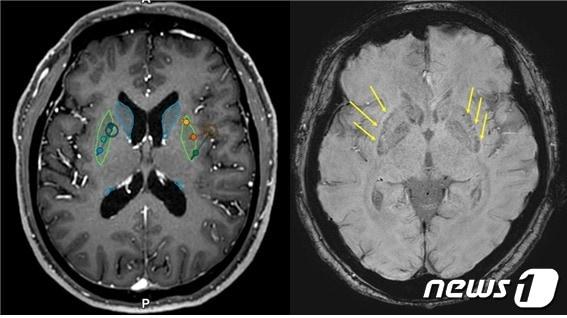

세브란스병원, 파킨슨병 환자에 배아줄기세포 치료제 뇌이식 성공